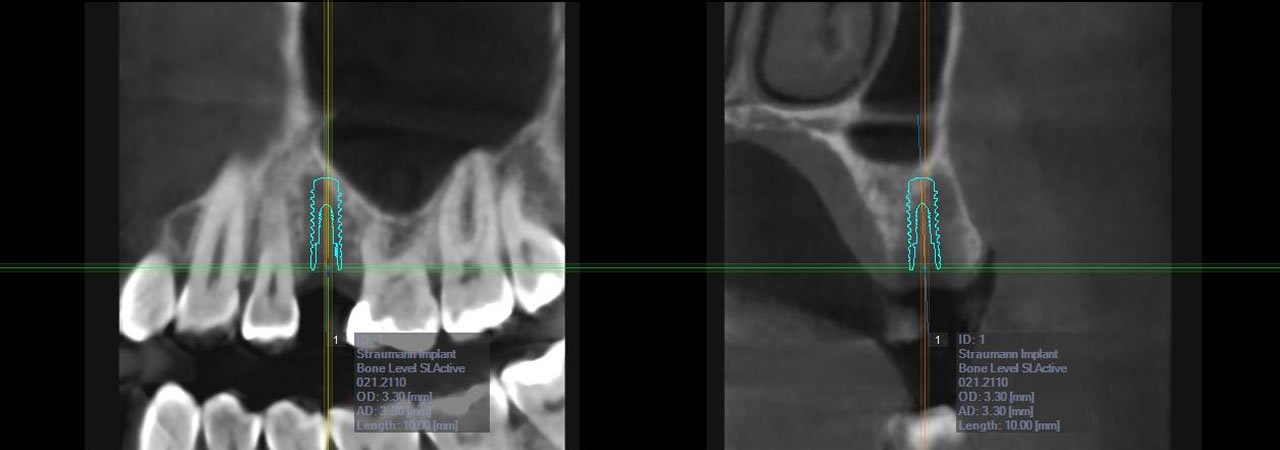

Im August 2021 haben wir unseren Digitalen Volumentomograph (DVT) in ein Modell neuester Bauart getauscht, der für Sie bei minimaler Strahlenbelastung optimale Bildqualität in 3D garantiert. 3D-Aufnahmen werden für komplexe Implantatplanungen bei schwierigen Knochenverhältnissen und bei stark verlagerten Weisheitszähnen benötigt. Dies ermöglicht:

- Software-basierte Simulation implantologischer Eingriffe